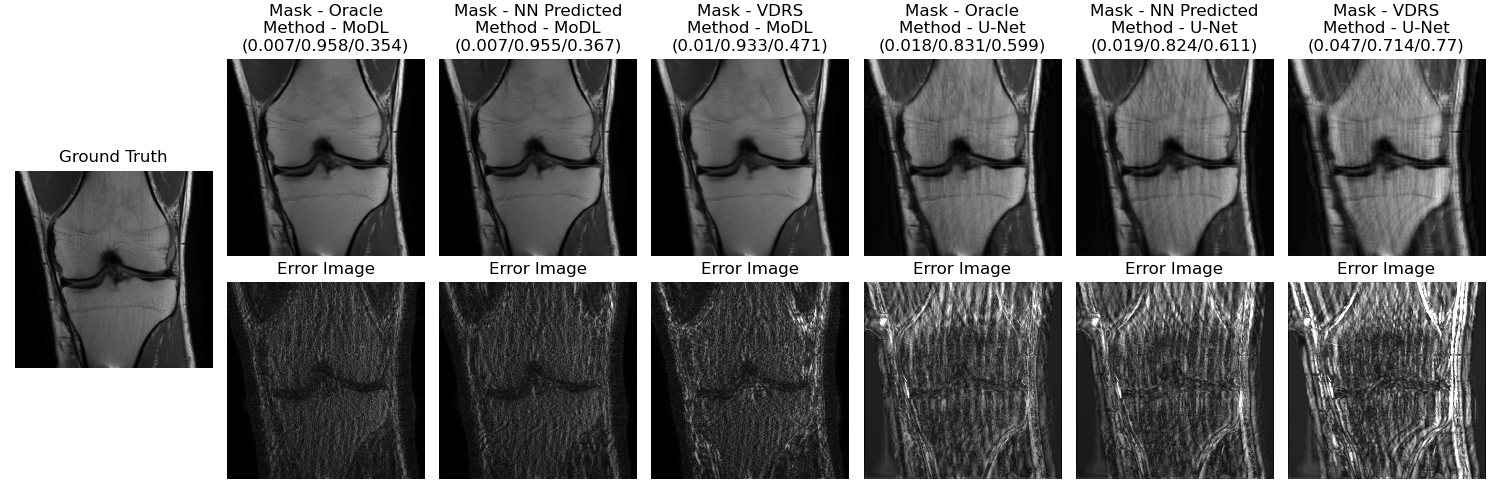

Refer to caption

Fig. 4: Reconstructed and (magnitude) error images for different combinations of masks and reconstructors. Reconstruction metrics shown are (NMSE/SSIM/HFEN)

1 shows the average NMSE, SSIM, and HFEN values over the test cases for different combinations of reconstructors and masks. Figure 4 shows reconstructed images for these combinations of different reconstructors and masks along with the error images for two different scans in the testing set.

Our results indicate better test-time reconstruction quality using an oracle (optimized directly using ICD for the test scan assuming known full k-space) and nearest neighbor sampling mask as compared to the conventional variable density random sampling (VDRS) mask in terms of NMSE, SSIM, and HFEN metrics, and visual quality (Figure 4). The test-time reconstructors used were the trained U-Net and MoDL networks.